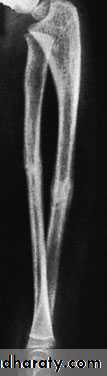

A-CHILDREN:In children, closed treatment is usually successful because the tough periosteum tends to guide and then control the reduction. The fragments are held in a well-moulded full-length cast, from axilla to metacarpal shafts (to control rotation). The cast is applied with the elbow at 90 degrees. The position is checked by x-ray after a week and, if it is satisfactory, splintage is retained until both fractures are united (usually 6–8 weeks).

Above elbow pop

Occasionally an operation is required, either if the fracture cannot be reduced or if the fragments are unstable. Fixation with intramedullary rods is preferred, but they should be inserted with great care to avoid injury to the growth plates. Alternatively, a plate or K-wire fixation can be used.